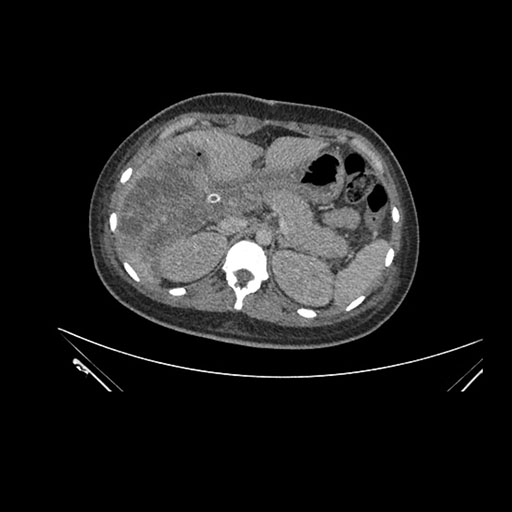

Imaging Analysis

Look through the patient's CT scan to identify any areas of concern for the necessary procedure.

Axial Venous

Based on initial findings, which issue(s) would you be most concerned about?